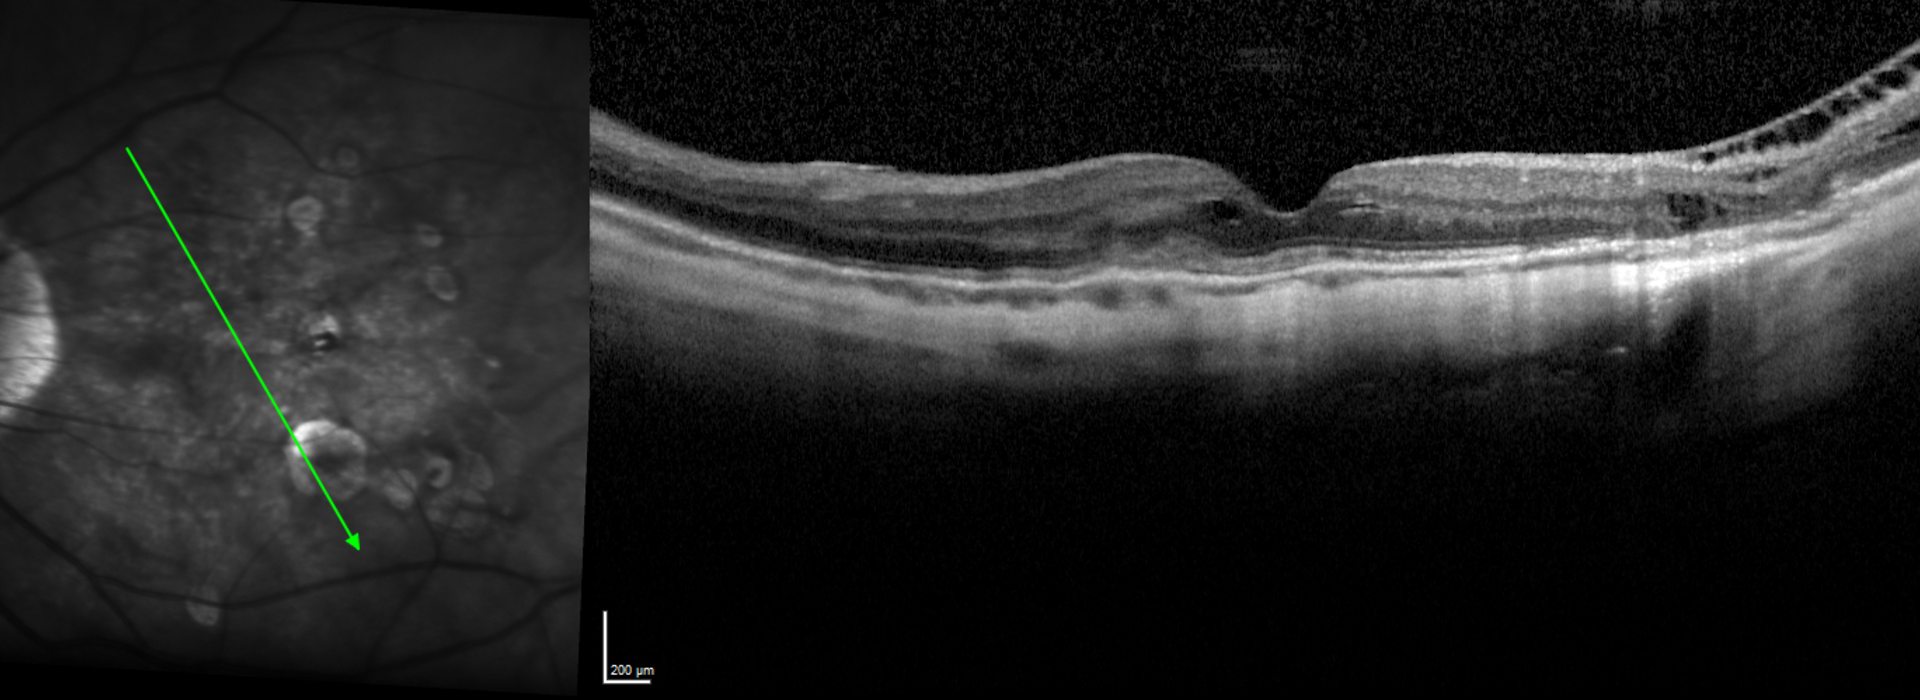

El Dr Juan Manuel Cubero describe el concepto de miopía patológica, los hallazgos estructurales que la definen y la utilidad de las diferentes pruebas de imagen para un correcto seguimiento y toma de decisiones tanto médica como quirúrgicas.

Particularidades del examen macular en miopía